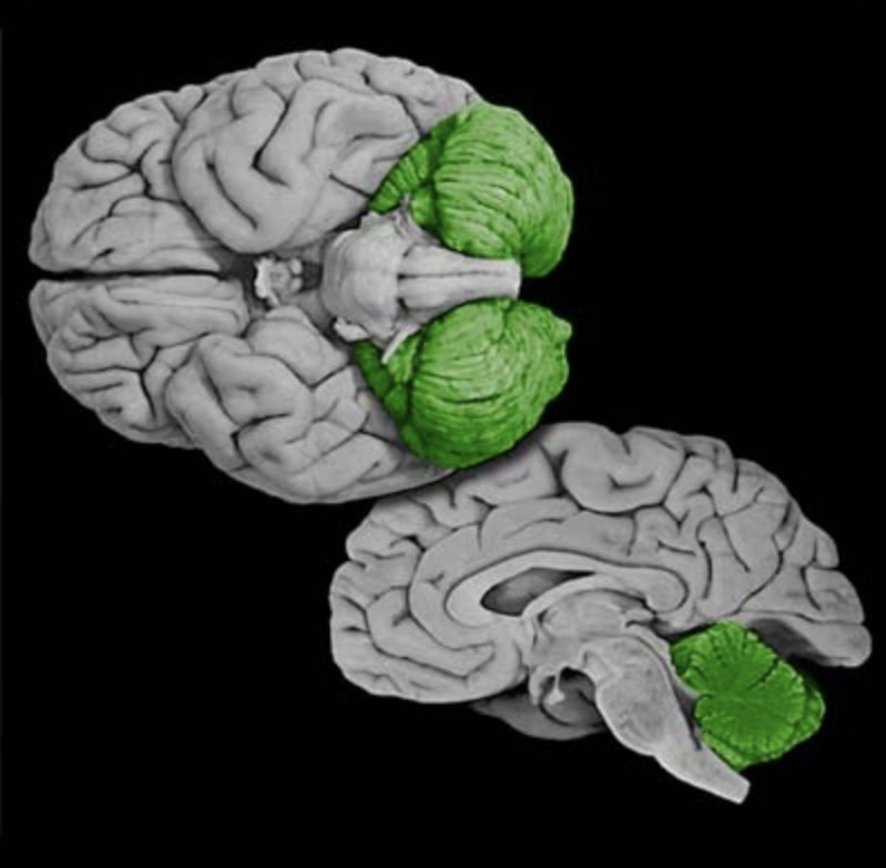

Lateral corticospinal tract

Decussating component (about 90% of total) of the corticospinal projection that originates in the motor cortical areas of the posterior frontal lobe and the postcentral gyrus. The lateral corticospinal tract is located in the lateral white column of the spinal cord and terminates in the lateral portion of the ventral horn, where it governs the lower motor neuronal pools that control the distal extremities.